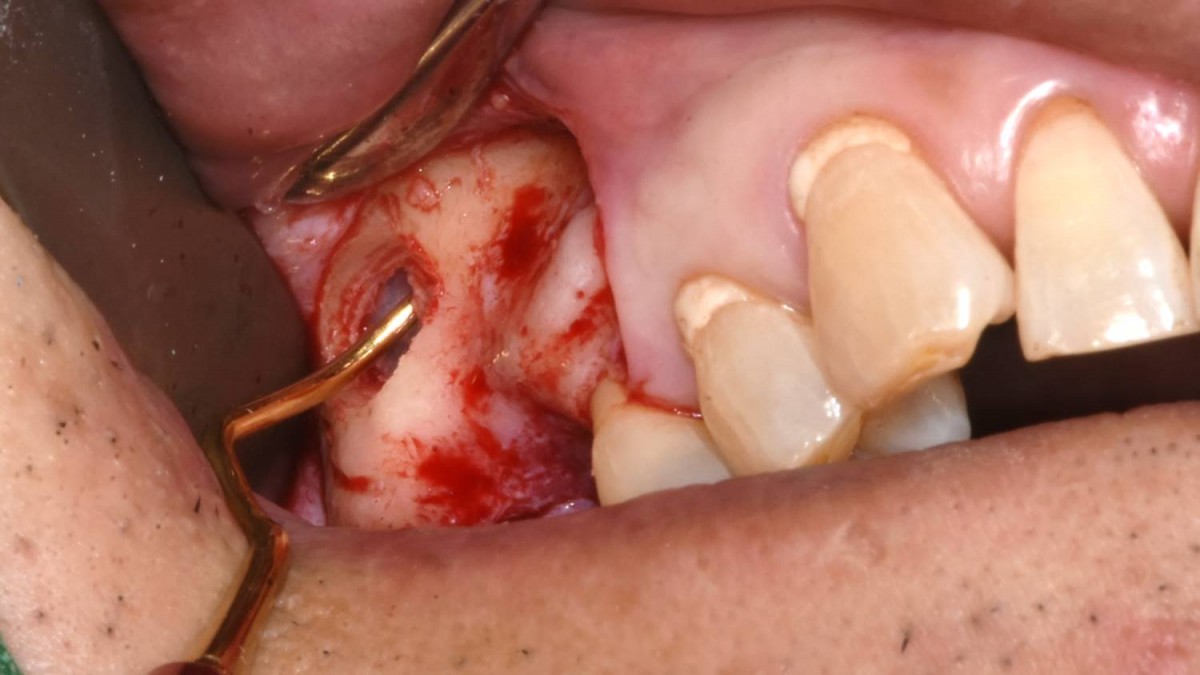

Maxillary Sinus Graft, 2 Implants, Crown Contouring

<GCaks> A 56-year-old male patient had pain-inducing caries, and perio-involved tooth mobility resulted in a tooth fracture at 1st molar. And it was removed months ago. He was a heavy smoker and showed poor oral hygiene.